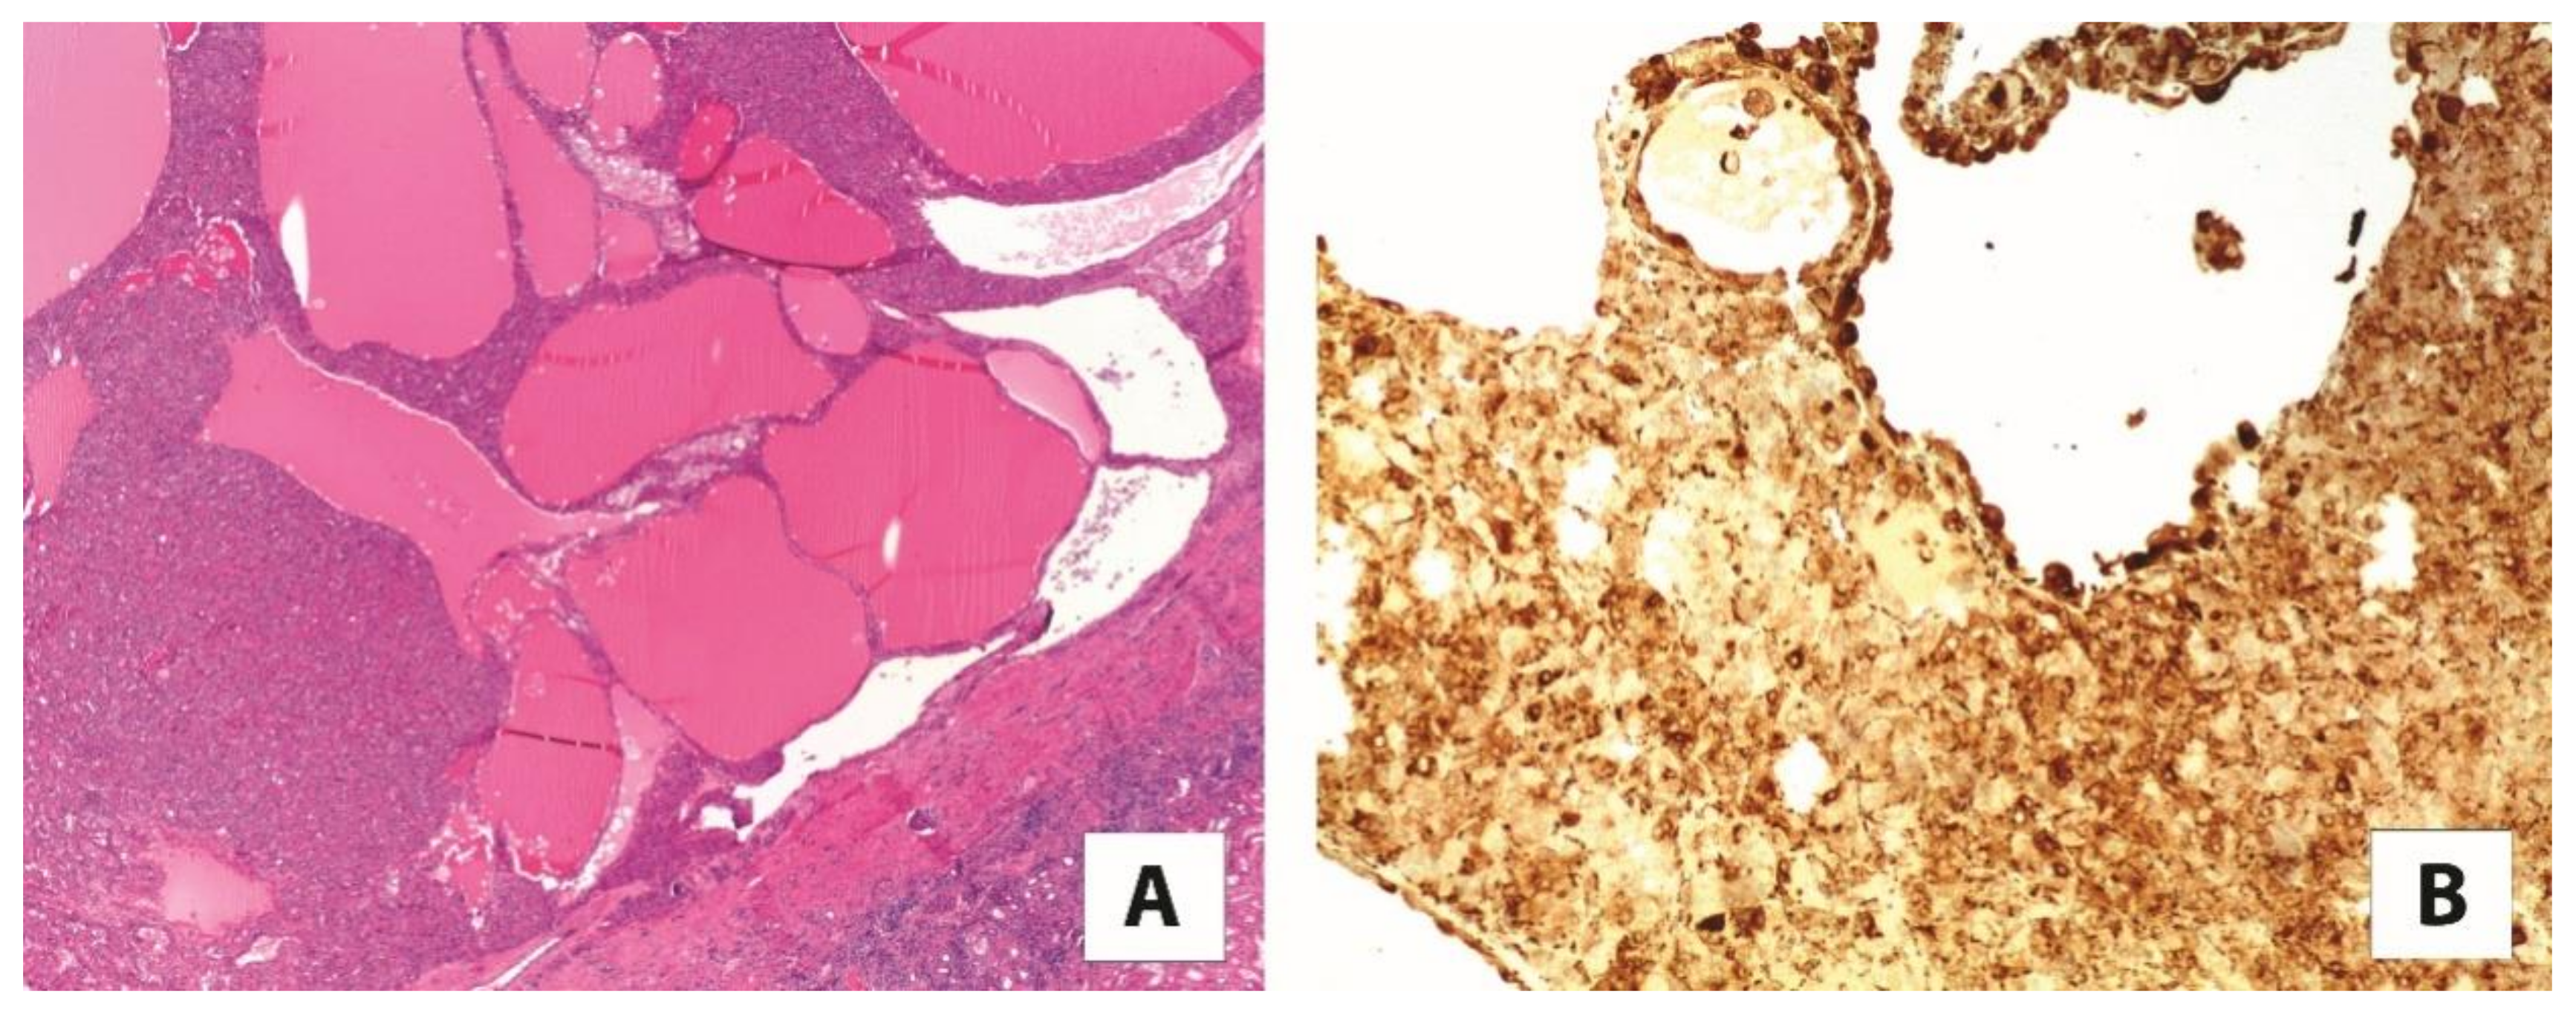

Translocation renal cell carcinomas comprise two different tumors molecularly characterized by specific gene translocations, namely TFE3-rearranged renal cell carcinoma, the most common subtype, and TFEB-rearranged renal cell carcinoma. As evidenced by their nomenclatures, they harbor TFE3 and TFEB gene fusions, respectively [28]. Initially, they were recognized in childhood; however, these neoplasms can arise in adults as well. TFE3-rearranged renal cell carcinomas display heterogeneous morphological features simulating most of the subtypes of renal cell carcinoma. The most distinctive histological characteristic of TFEB-rearranged renal cell carcinoma is the biphasic appearance: nests of large epithelioid cells and smaller cells clustered around hyaline nodules formed by a basement membrane material that is collagen IV positive. Nevertheless, it is widely accepted that both TFE3-rearranged renal cell carcinoma and TFEB-rearranged renal cell carcinoma may show a broad range of morphology, resulting in a challenging differential diagnosis. Currently, cathepsin K immunostaining is generally used by uropathologists to reach the proper diagnosis of translocation renal cell carcinoma [1,29]. Indeed, cathepsin K is expressed in roughly half of TFE3-rearranged renal cell carcinomas, and is observed in virtually all TFEB-rearranged renal cell carcinomas (Figure 1). In the beginning, the idea of the cathepsin K expression in translocation renal cell carcinoma was postulated based on the consistent ability of MiTF to modulate the cathepsin K gene promoter in osteoclasts. As the target DNA sequences of MiTF overlap with those of TFE3 and TFEB, it has been hypothesized that the overexpressed TFE3 fusion proteins or native TFEB in these renal cell carcinomas may have the same effect on the promoter of cathepsin K.

Figure 1. An example of (A) TFE3-rearranged renal cell carcinoma with papillary architecture (5×), (B) strongly and diffusely positive for cathepsin K (20×).